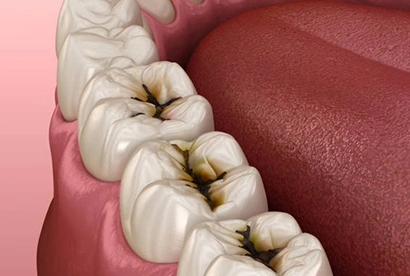

Caries Detection

Our caries detection device allows us to diagnose and manage areas of decay at the earliest possible stages. In some cases, we can even successfully treat the area with preventive intervention.